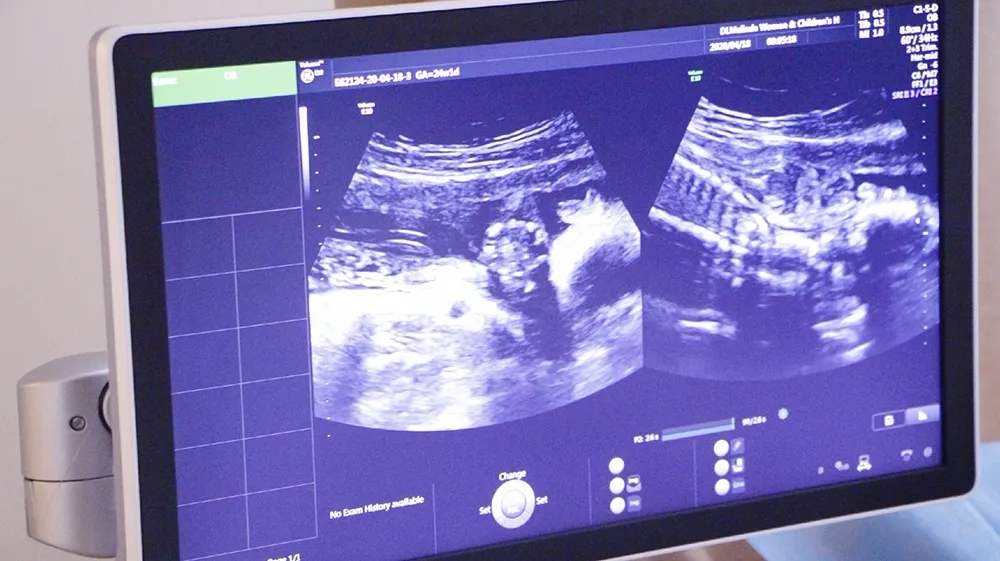

四维彩超是超声检查的一种,是孕期(zui)重要的一次超声检查,一般在孕24周进行,除了一般彩超的功能外,还可以进行胎儿头面部立体成像,可协助医生直接对胎儿先天畸形进行诊断,包括表面畸形、内脏畸形和头面部畸形,可实时观察胎儿动态的活动图像。

二维超声它是一个切面的成像,三维是在二维的基础上面提供一个立体的成像,而四维彩超就是在三维的基础上又加了一个时间的动态,多用于为胎儿拍照和录像以满足家长见到胎儿形象的愿望。

引进美国进口系列设备-清晰动态记录胎宝美琳达超声科引进多台美国GE-E10、美国GE-E8等系列机器。能够提高细节分辨率,实现在扫描同时即刻呈现胎儿标准生长曲线和相应测量数据。满足从早孕期研究到复杂胎心的全程早期检查和诊断,通过四维立体成像,清晰并动态记录宝宝在子宫内的活动和成长历程。